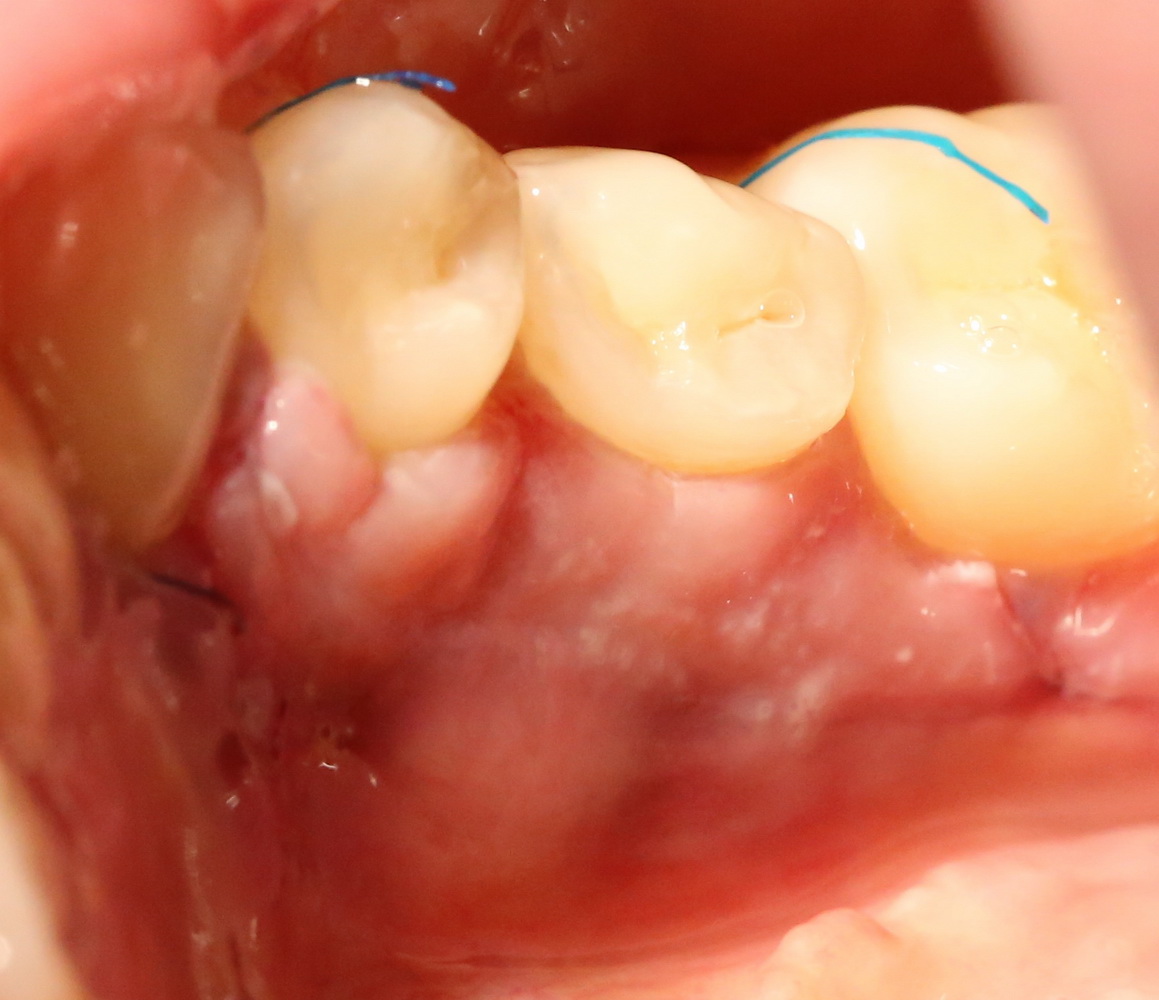

А вот фотография через месяц после операции:

Задайтесь вопросом — оно того стоило? 30 минут в операционной, 4 дня на реабилитацию и 2 недели со швами? Стоило ли это того, чтобы в будущем избежать серьезных проблем со здоровьем?

На мой взгляд — да.